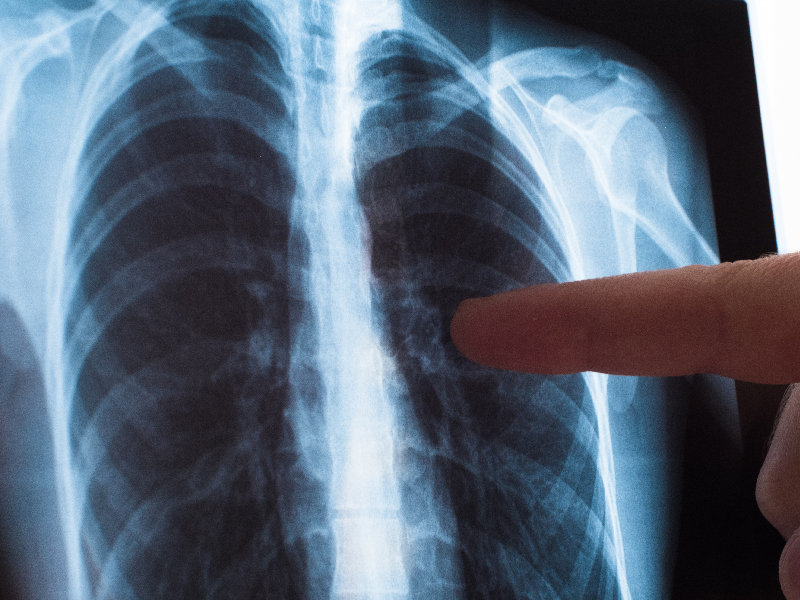

"Dengan salah satu gejala yang disebut tadi sudah perlu dicurigai mengidap TBC. Dan untuk di era sekarang yang mungkin kondisi ekonomi sudah lebih baik dari era dahulu sering ditemui pasien dengan tanpa gejala, hanya karena sedang melakukan MCU dan dengan hasil foto thorax ternyata ditemukan pasien sudah mengidap TBC," lanjut dokter yang akrab disapa dokter Anke.

Jika orang sudah datang dengan keluhan batuk darah, sesak nafas, nyeri dada, berat badan turun, ada kondisi lemas. Maka harus segera dilakukan pemeriksaan lanjutan, yaitu dilakukan pemeriksaan dahak dan pemeriksaan radiologi atau foto dada.

Setelah pasien sudah menyelesaikan pengobatan TB nya akan dilakukan foto thorax lanjutan di bulan ke-6 dan bulan ke-12 serta di bulan ke-24. Jadi dalam dua tahun tetap harus di evaluasi kondisi pasien apakah terjadi kasus kambuhan atau tidak. TBC ini bisa menyebabkan kekambuhan walaupun sudah sembuh. Untuk itu perlu dilakukan evaluasi dengan baik.